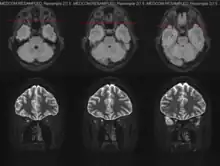

Imaging

Imaging of the optic nerve with MRI shows increased signal on the affected side. There is contrast enhancement of the symptomatic optic nerve and sheaths acutely or intrinsic signal increase (looking brighter) within ≥ 3 months.[1]